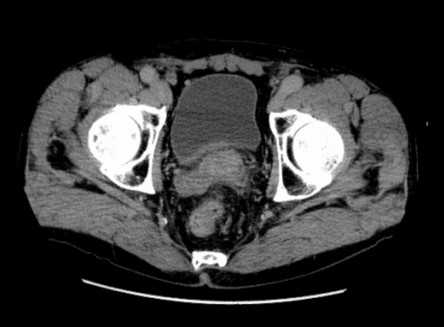

Клинический случай 1

Пациент С., 1945 года рождения, считает себя больным с 2012 г., когда впервые отметил затруднения при мочеиспускании, однако к врачам не обращался. В июле 2016 г. при плановом обследовании по месту жительства выявлено повышение ПСА до 276 нг/мл, выполнена трансректальная биопсия предстательной железы под ультразвуковым контролем. Больной для дальнейшего обследования и лечения обратился в поликлинику МНИОИ им. П.А. Герцена. При гистологическом исследовании, пересмотре стекол и блоков гистологических препаратов в МНИОИ им. П.А. Герцена выявлен инфильтративный рост ацинарной аденокарциномы 7 (4+3) баллов по Глисону, занимающей до 80% площади биоптатов. Пациент самостоятельно выполнил ПЭТ/КТ с холином. По данным ПЭТ/КТ, в обеих долях простаты определяются очаги накопления радиофармпрепарата (РФП) неоднородного характера, с наиболее выраженным накоплением РФП до макс. SUV 12,09 в периферической зоне слева и переходных зонах предстательной железы с обеих сторон (рис. 1), Рис. 1. Компьютерная томограмма малого таза (а). Накопление РФП в предстательной железе (б). в семенных пузырьках слева и справа, а также в наружном подвздошном лимфатическом узле слева макс. SUV 4,47, размером 1,3×0,7 см.